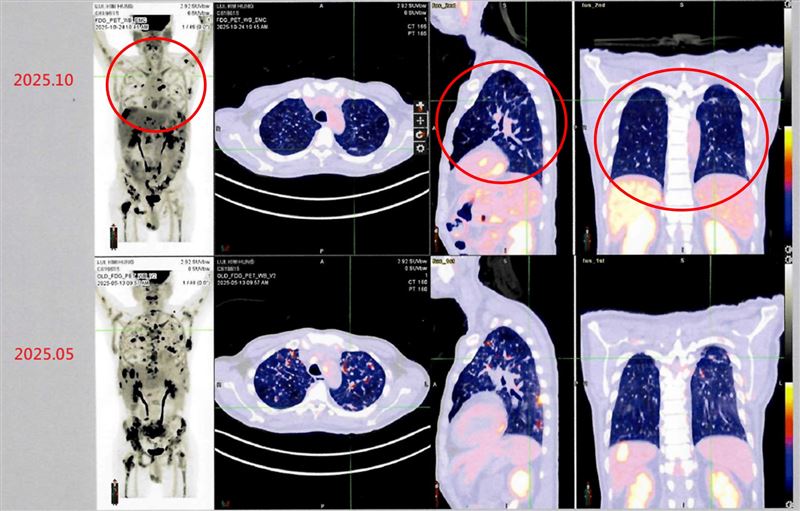

衛生福利部雙和醫院一名來自香港的50歲男性病患,2024年在香港被診斷出罹患第四期肺癌,歷經多次傳統化療與標靶治療後。為了尋求新的治療機會,他決定來台灣進行自體免疫細胞治療(DC-CIK),透過半年整合療程後,最新影像檢查顯示病情穩定,疼痛症狀明顯獲得緩解,體能與生活品質大幅提升。